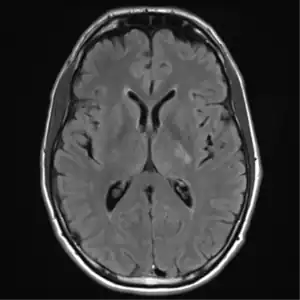

![]() ![]() text: From left to right: Cryptococcosis lung, cryptococcosis brain | |

MRI brain: cryptococcus -